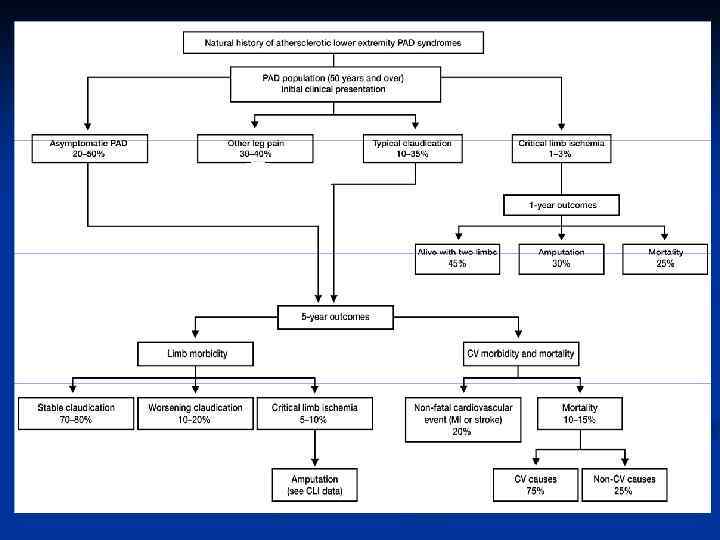

Частота оклюзивних захворювань артерій нижніх кінцівок у старшій віковій групі може сягати 23%, серед яких у 20 -40% розвивається ХКІНК (Management of Peripheral Disease (РАD), Trans Atlantic Inter–Society Working Group (ТАSС), 2000), досягаючи 600 -800 на 1 млн. жителів (Critical limb ischaemia: comments on consensus document, 1991).

Частота оклюзивних захворювань артерій нижніх кінцівок у старшій віковій групі може сягати 23%, серед яких у 20 -40% розвивається ХКІНК (Management of Peripheral Disease (РАD), Trans Atlantic Inter–Society Working Group (ТАSС), 2000), досягаючи 600 -800 на 1 млн. жителів (Critical limb ischaemia: comments on consensus document, 1991).

n n Скандинавські країни: частота ХКІНК 800 на 1. 000 населення, з них у 200 випадках (кожний 4 -й) виконують високі ампутації кінцівок (Fagrell B. , 2006). В Англії та Ірландії частота виникнення ХКІНК сягає 400 випадків на 1. 000 населення, при цьому летальність та ампутації кінцівок складають відповідно 13, 5% та 21, 5 % (Tiepe G. , 2001). З приводу ХКІНК у Європі щорічно оперують близько 171. 000 хворих з ХКІНК, кількість ампутацій 150 -280 на 1 млн. населення, у США – 160. 000 реконструкцій, до 200 ампутаций на 1 млн. населення в рік. Витрати на лікування ХАН кінцівок складають 2, 5 млн. $ на 1 млн. населення. у Швейцарії – кількість ампутацій 140 на 1 млн. населення, в Росії – близько 8. 000 реконструкцій, 30 -40 тис. ампутацій (з частотою >500 на 1 млн. в Москві). у Фінляндії - кількість ампутацій 164 на 1 млн. населення Витрати при первинній ампутації кінцівки у США вдвічі перевищують витрати при успішній реваскуляризації (Stillman R. M. , 2001).

n n Скандинавські країни: частота ХКІНК 800 на 1. 000 населення, з них у 200 випадках (кожний 4 -й) виконують високі ампутації кінцівок (Fagrell B. , 2006). В Англії та Ірландії частота виникнення ХКІНК сягає 400 випадків на 1. 000 населення, при цьому летальність та ампутації кінцівок складають відповідно 13, 5% та 21, 5 % (Tiepe G. , 2001). З приводу ХКІНК у Європі щорічно оперують близько 171. 000 хворих з ХКІНК, кількість ампутацій 150 -280 на 1 млн. населення, у США – 160. 000 реконструкцій, до 200 ампутаций на 1 млн. населення в рік. Витрати на лікування ХАН кінцівок складають 2, 5 млн. $ на 1 млн. населення. у Швейцарії – кількість ампутацій 140 на 1 млн. населення, в Росії – близько 8. 000 реконструкцій, 30 -40 тис. ампутацій (з частотою >500 на 1 млн. в Москві). у Фінляндії - кількість ампутацій 164 на 1 млн. населення Витрати при первинній ампутації кінцівки у США вдвічі перевищують витрати при успішній реваскуляризації (Stillman R. M. , 2001).